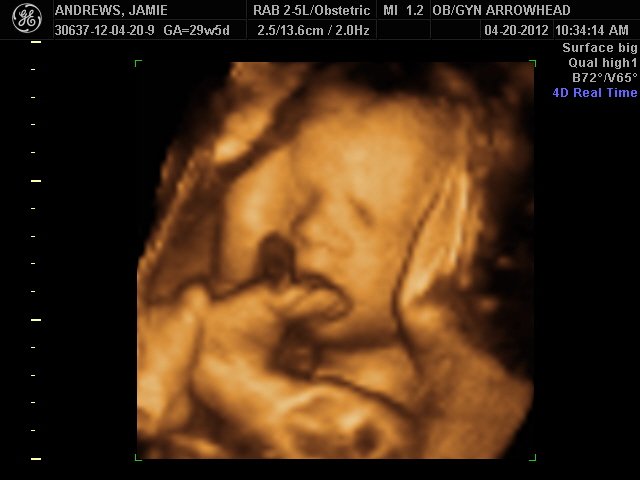

We offer complimentary 3D/4D Ultrasounds to all our OB patients around 30 weeks! The following photos are some examples of our work, shown with permission from our patients.